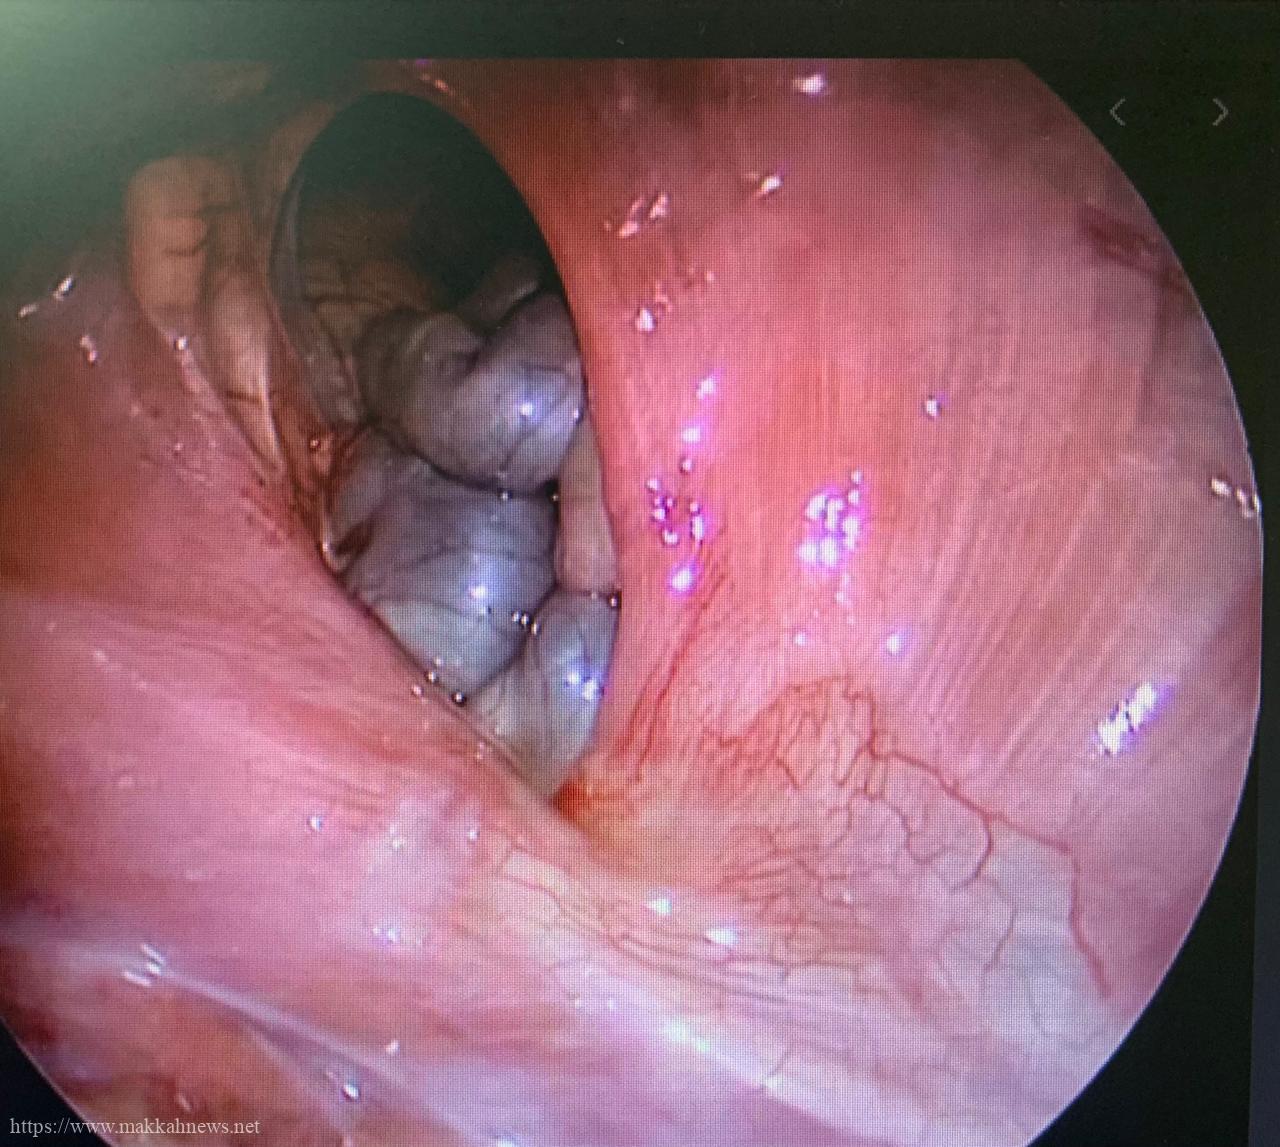

نجح فريق طبي بمستشفى الولادة والأطفال بمكة عضو التجمع الصحي بمكة المكرمة من إصلاح فتق بالحجاب الحاجز لطفلة تبلغ من العمر 6 أيام بإستخدام منظار الصدر الجراحي جاء ذلك بقيادة رئيس الفريق الطبي الدكتورعبدالرحمن مغربي ومشاركة نخبة رائدة من الأطباءكما أوضح رئيس الفريق الطبي الدكتورعبدالرحمن مغربي أن هذه العملية تعد من العمليات النادرة حيث تم إرجاع الأمعاء والمعدة والطحال من التجويف الصدري الأيسر ورتق الفتحة الخلفية الموجودة بالحجاب الحاجز بإستخدام منظار الصدرالجراحي

وأردف مدير مستشفى الولادة والأطفال بمكة الدكتور هلال المالكي قائلا نظراً لندرة العملية و التي تعد تحدياً كبيراً للفريق الطبي. ولكن بفضل الله تكللت العملية بالنجاح و بدون حدوث أي مخاطر أثناء وبعد العملية وخرجت الحالة بسلام من المستشفى بعد 6 أيام من إجراء العملية وهي تتمتع بصحة ممتازة ولله الحمدكما ثمن الدكتورالمالكي هذا الإنجاز لافتاً سعي مستشفى الولادة والأطفال لتقديم خدمات طبية متميزة في ظل توجيهات خادم الحرمين الشريفين وولي عهده. والتي يجعلها مقصداً لكثير من المرضى